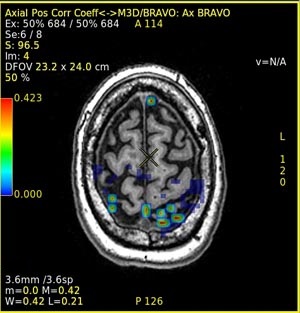

Figure 2. Example of activation map fused to anatomical image